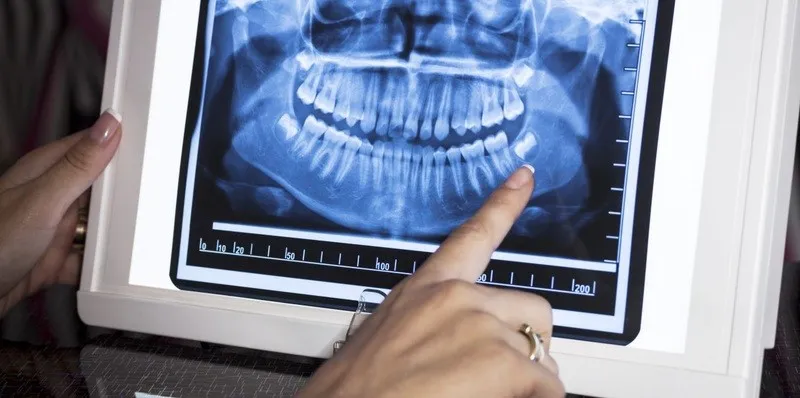

Chụp X quang răng là điều cần thiết khi thực hiện các phương pháp nha khoa hiện nay. Phương pháp này giúp cho nha sĩ nắm rõ

Chụp X-quang răng là bước quan trọng trong việc chẩn đoán và điều trị các vấn đề về răng miệng, giúp bác sĩ xác định chính xác